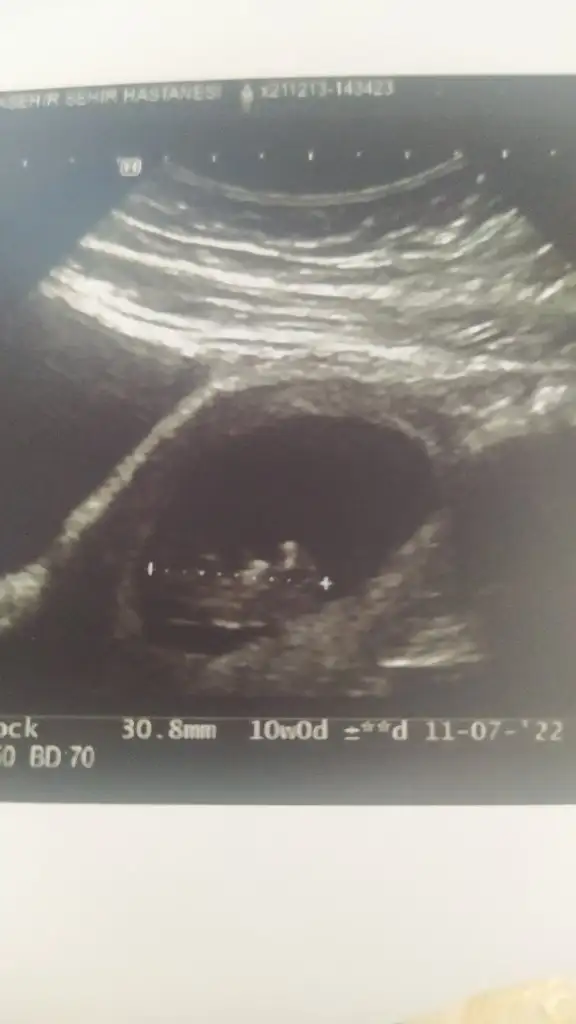

10+6 nub teorisine gore cinsiyeti nedir

• IMG_20211222_120246.webp